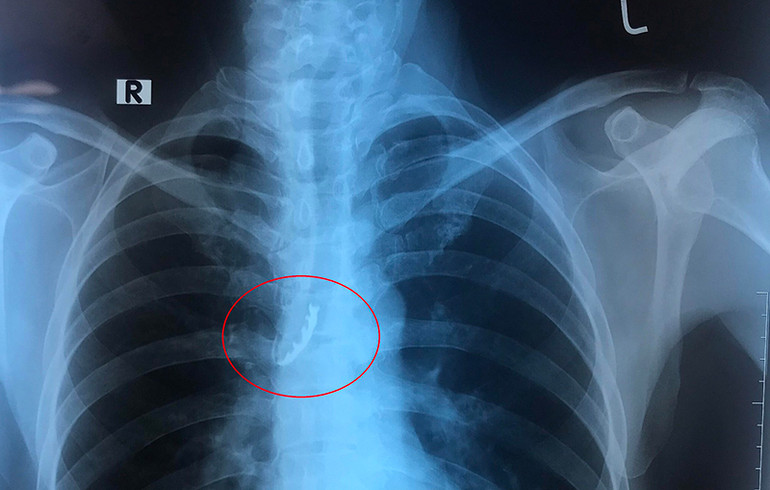

Phim chụp dị vật là bốn chiếc răng giả trong phế quản của bệnh nhân.

Các bác sĩ đã khám và thực hiện cận lâm sàng xác định vị trí dị vật, đồng thời tiến hành hội chẩn các chuyên khoa: Tai mũi họng, Nội hô hấp, Phẫu thuật – Gây mê hồi sức với chẩn đoán Dị vật đường hô hấp. Bệnh nhân có chỉ định nội soi phế quản ống mềm có gây tê để lấy dị vật do BS, CK1 Nguyễn Văn Tuyết – Phó Trưởng Khoa Nội hô hấp thực hiện. Sau 30 phút nội soi, bác sĩ đã can thiệp lấy thành công bốn chiếc răng giả “bị lạc” vào gốc phải của phế quản.